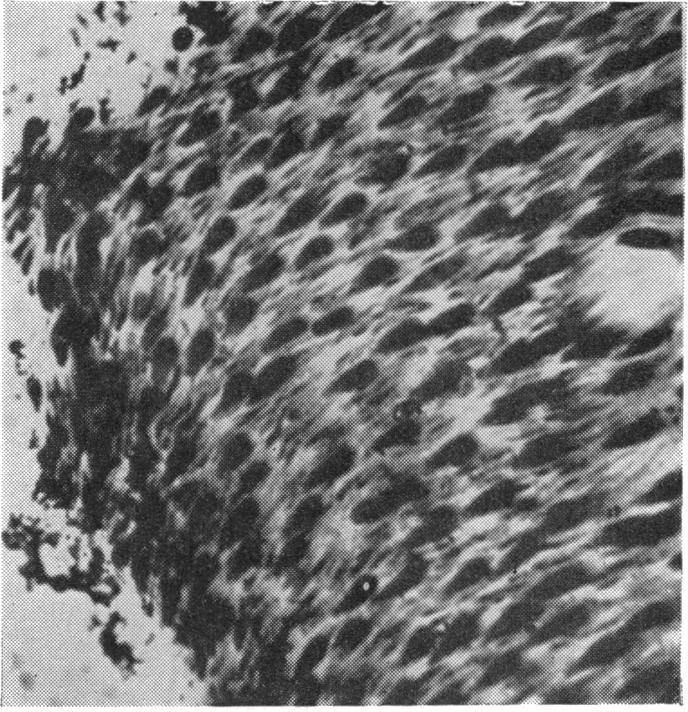

RETINAL PATHOLOGY AFTER CENTRAL RETINAL VEIN OCCLUSION.

Br J Ophthalmol. 1961 Oct;45(10):683-94. doi: 10.1136/bjo.45.10.683.